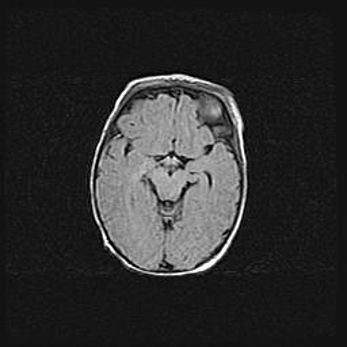

Сообщающаяся гидроцефалия. Кистозная энцефаломаляция головного мозга.

Возраст: 3 месяца 4 дня

Вес: 3100 г

Пол: женский

Окружность головы: 34 см

Срок гестации: 31 неделя

Кистозная энцефаломаляция головного мозга - одна из форм поражения головного мозга в детском возрасте. Характеризуется возникновением множественных и распространённых кист в коре, белом веществе и подкорковых образованиях головного мозга у плодов, новорождённых и детей раннего возраста. Развитие кистозной энцефаломаляции связано с внутриутробной асфиксией и гипотонией, родовой травмой, тромбозом синусов, пороками развития сосудов, инфекциями, сепсисом и другими причинами. Наиболее значимые инфекционные агенты: вирусы простого герпеса, цитомегалии, краснухи, токсоплазмы, энтеробактерии, золотистый стафилококк и другие.